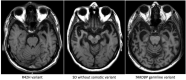

The aetiology of late-onset neurodegenerative diseases is largely unknown. Here we investigated whether de novo somatic variants for semantic dementia can be detected, thereby arguing for a more general role of somatic variants in neurodegenerative disease. Semantic dementia is characterized by a non-familial occurrence, early onset (<65 years), focal temporal atrophy and TDP-43 pathology. To test whether somatic variants in neural progenitor cells during brain development might lead to semantic dementia, we compared deep exome sequencing data of DNA derived from brain and blood of 16 semantic dementia cases. Somatic variants observed in brain tissue and absent in blood were validated using amplicon sequencing and digital PCR. We identified two variants in exon one of the TARDBP gene (L41F and R42H) at low level (1-3%) in cortical regions and in dentate gyrus in two semantic dementia brains, respectively. The pathogenicity of both variants is supported by demonstrating impaired splicing regulation of TDP-43 and by altered subcellular localization of the mutant TDP-43 protein. These findings indicate that somatic variants may cause semantic dementia as a non-hereditary neurodegenerative disease, which might be exemplary for other late-onset neurodegenerative disorders.